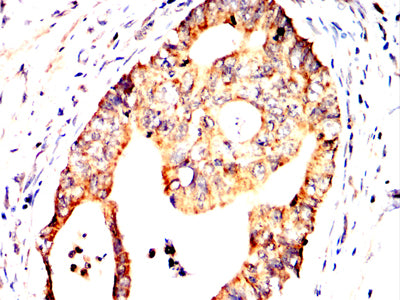

分类: 科研抗体货号: 32361别名: CT132; SPAS1; spergen1应用: IHC反应种属: Human